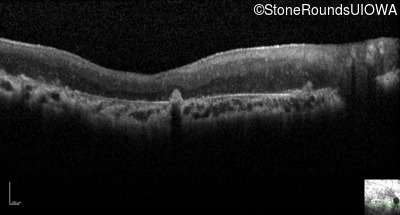

Optical Coherence Tomography - Right - Light Perception

Exemplar

Optical Coherence Tomography - Left - Light Perception